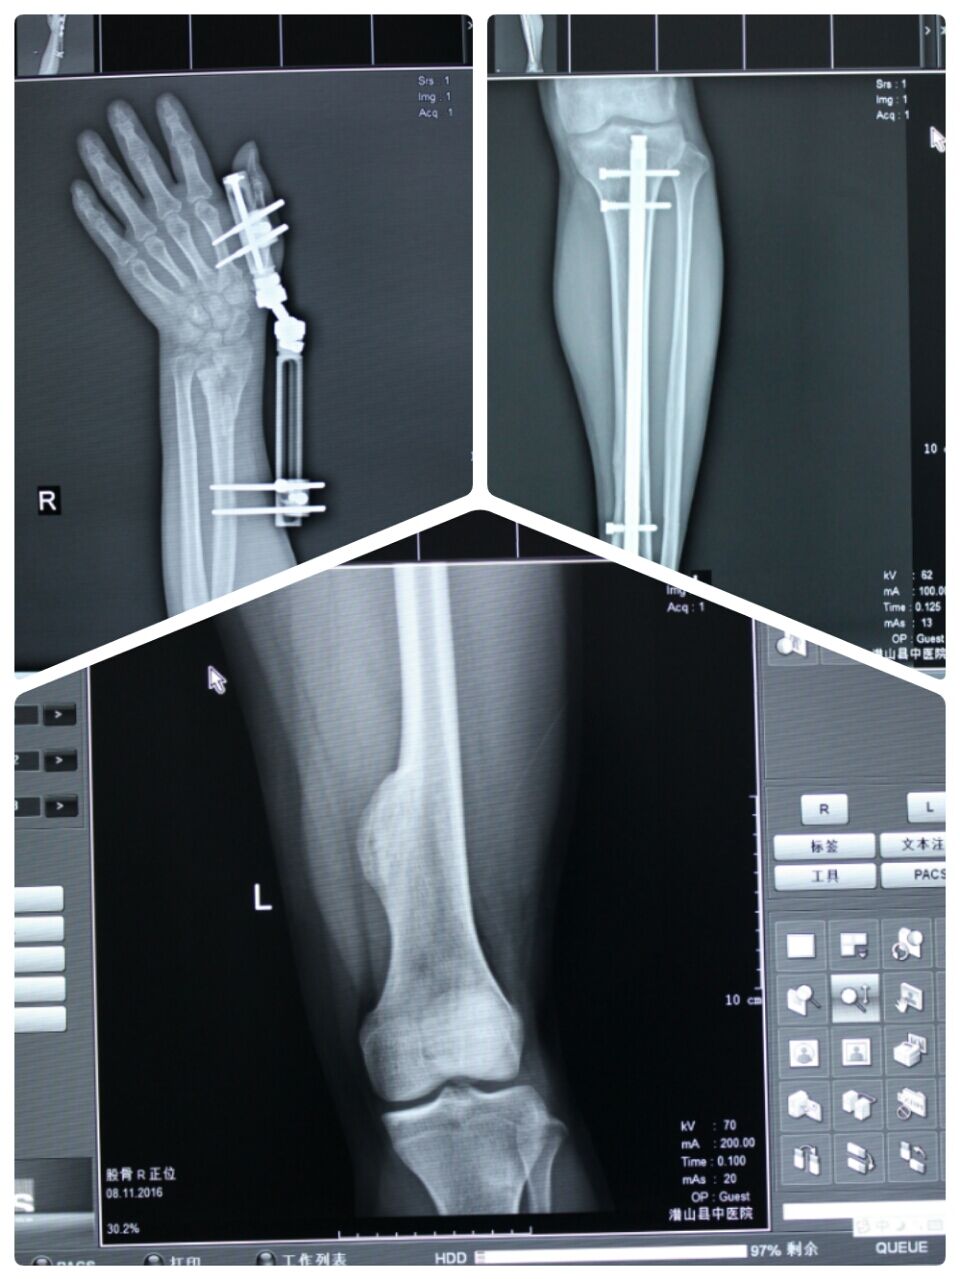

近日,我院放射科引进韩国(MIS)公司最新MXHF-1800双板数字化直接成像系统(DR)设备,并已安装调试成功,正式投入临床使用。

该设备集尖端技术于一身,可以最大限度地满足我院临床影像检查的要求(包括立位、卧位、担架位全方位的影像检查),具有浮动床面检查平台、同步升降跟踪、床下探测器自动跟踪功能,减少了患者在检查时的不必要搬动,让患者更加舒适。该系统图像清晰、分辩率高、对比度高、层次丰富、操作简便、成像时间短,能准确及时地为临床医师提供患者的医学影像素材,极大提高了我院临床诊断水平,大大缩短了患者的候诊时间,同时提升了医院服务质量,这也是我院进一步改善医疗服务行动,创建中医名院的重要措施之一。(放射科 钟诚 供稿)